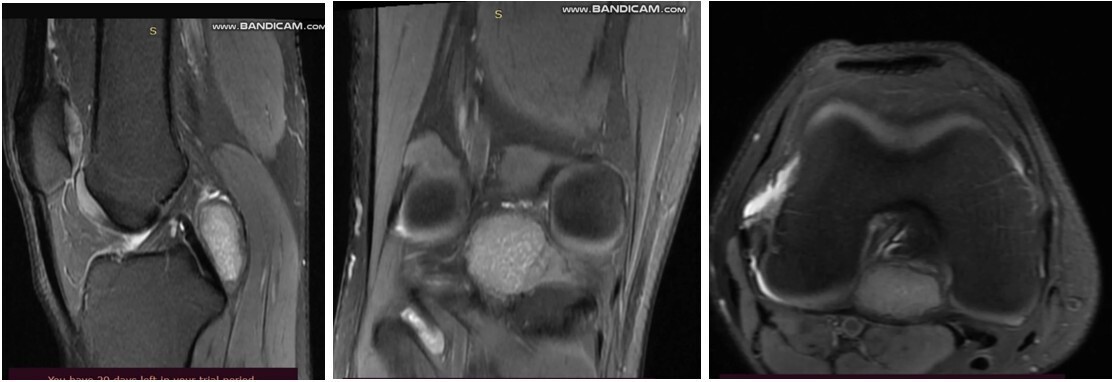

Radiographs demonstrated a subtle radio-opaque circular shadow located just posterior to the tibial slope (Fig. 1). T2-weighted MRI imaging revealed a well-defined lesion with heterogeneous signal intensity, measuring 1.4 × 2.5 × 3 cm. The lesion was situated in the midline posterior compartment, anterior to the knee capsule, and in close proximity to the posterior cruciate ligament (PCL) (Fig. 2). The differential diagnoses included ganglion cyst, Baker’s cyst, parameniscal cyst, PVNS, lipoma arborescens, synovial hemangioma, early-stage SC, and soft-tissue neoplasms such as synovial sarcoma or chondrosarcoma. The patient underwent a computed tomography torso and chest radiograph, which revealed no evidence of primary malignancy or metastasis.

Figure 2: T2-weighted magnetic resonance image of the knee demonstrating a well-defined lesion with heterogeneous signal intensity. The lesion is located in the midline posterior compartment, anterior to the knee capsule, and closely abutting the posterior cruciate ligament.